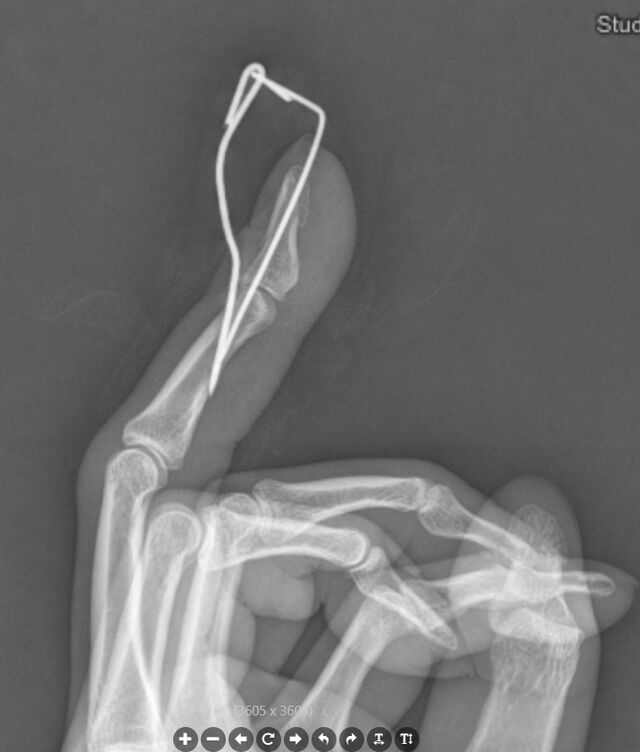

丁香园战友的作品

传统石黑法,预弯克氏针防止压皮

微信图片_20240206223541.png